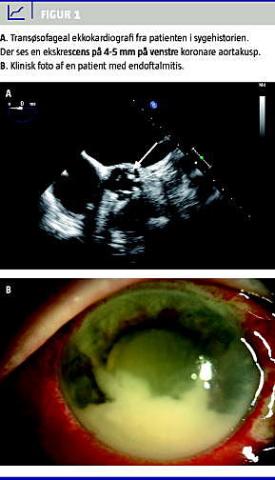

En efterfølgende udredning med transøsofageal ekkokardiografi viste en 4-5 mm stor ekskrescens på venstre koronare aortakusp, moderat aortainsufficiens og let ikke hæmodynamisk betydende mitralinsufficiens (Figur 1 A). På kardiologisk afdeling blev der iværksat systemisk antibiotikabehandling, mens patientens endoftalmitis blev behandlet med intravitreale og topikale antibiotika. Bloddyrkninger og mikrobiologisk svar fra vitrektomien viste hæmolytiske streptokokker gruppe B, følsomme for penicillin. Som led i fokusjagt udførte man en positronemissionstomografi-computertomografi og efter mikrobiologisk anbefaling undersøgelse af tænder, genitalia og urinveje, uden at der blev fundet et sikkert primært infektiøst fokus.

EE er en infektion i øjenæblet og en frygtet komplikation inden for oftalmologien [4]. Tilstanden er sjælden (2-8% af alle tilfælde af endoftalmitis) [4] og opstår oftest på baggrund af bakteriæmi eller fungæmi med hæmatogen spredning til øjet. Sympto-merne er hyppigt smerter og sløret syn og kan være ledsaget af fotofobi og »fluer« i synsfeltet. Ved objektiv undersøgelse finder man ofte ciliær injektion, hypopyon og uklar ødematøs cornea [4] (Figur 1B). Diagnosen stilles ved biopsi fra glaslegemet eller vi-trektomi. Ved EE med bakteriæmi skal behandlingen være systemisk suppleret med intravitreal injektion af antibiotika og topikale antibiotika. Synsprognosen er generelt dårlig og afhænger af infektiøst agens, virulens og visus ved symptomdebut [4, 5].